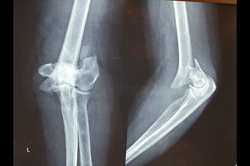

Elbow